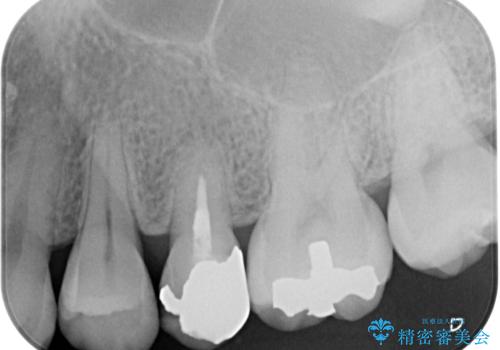

銀歯の歯は既に根管治療がされており、根尖部に病変が認められないため、根管治療を行うことなくオールセラミッククラウンにて補綴治療を行うこととしました。

むし歯の症状のある歯は、ややしみることがある程度でしたが、レントゲン写真では非常にむし歯が大きく、神経組織に迫っている状態でした。

術前診査では神経を全て取る可能性は低いと予想されましたが、一部切除する可能性があることを伝えた上で治療を行うこととしました。